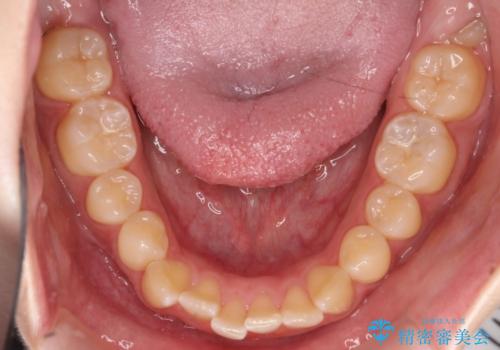

【インビザライン】オープンバイト。凸凹を治したい

- オープンバイトを主訴に来院されました。

インビザラインを用いIPRと遠心移動を行いオープンバイトと叢生の改善を行なっております。

前歯の叢生がわずかにありますが、追加アライナーの作成は希望されなかったため、歯を動かしていく動的治療は終了となりました。